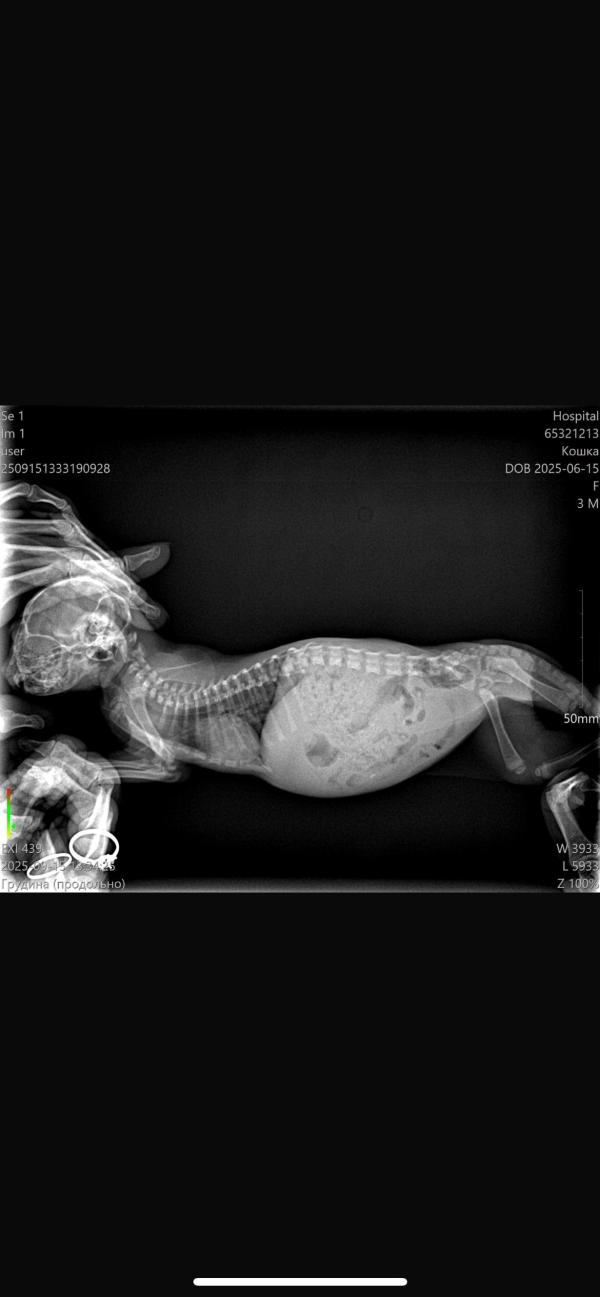

Вет. Врачи хочу с вами проконсультироваться, у котенка ужасные хрипы при дыхании, назначили сначала промывание, не помогло, потом антибиотик кладакса, не помогло, рентген сделали только вчера, не понимаю почему раньше нельзя было этого сделать, теперь колим гормон «так как все идет к отеку легких», и параллельно даем тот же препарат( все по рекомендации врача) вчера и сегодня сделали укол, но она все равно ооочеент тяжело дышит, в моменте когда она успокаивается, дыхание вроде как умеренное но какие-то хрипы присутствуют. Настолько тяжело, что порой вытягивает голову либо вперед либо вверх и пытается вдохнуть

Судя по описанию состояния (очень тяжело дышит даже после гормона и антибиотика), это может быть либо выраженная пневмония с дыхательной недостаточностью, либо отёк лёгких, либо жидкость в плевральной полости.

Все эти варианты требуют кислородной поддержки и интенсивной терапии в стационаре. Домашнее лечение в такой ситуации обычно не спасает, потому что котёнку реально не хватает воздуха.